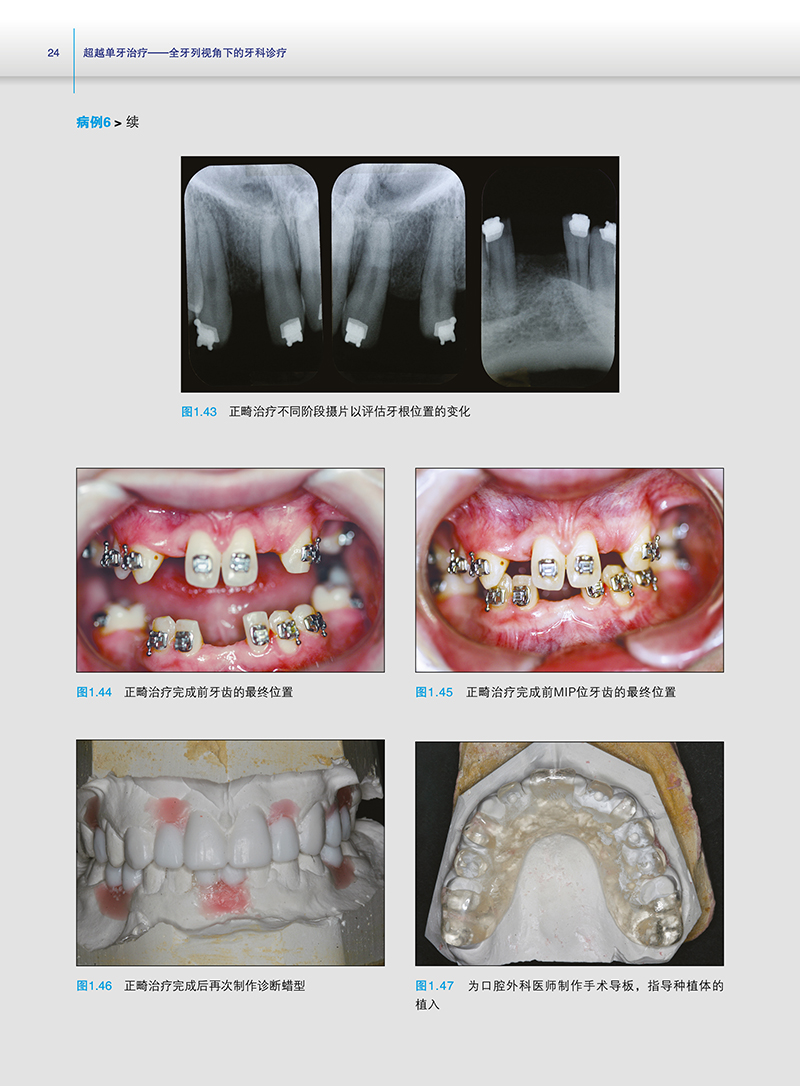

如果您有以上困惑,本书就是您的临床帮手!它能帮您突破“单一学科牙科学”局限,升级为“跨学科牙科学”,联合多学科有序协作,为患者提供全面诊断并制订综合治疗计划。全书共8章,搭配21个典型病例、大量高清图片及10余份详细表格,系统讲解全面诊断、综合治疗计划制定、多学科协作团队组建,助您掌握跨学科牙科诊疗,为临床工作带来新启发。